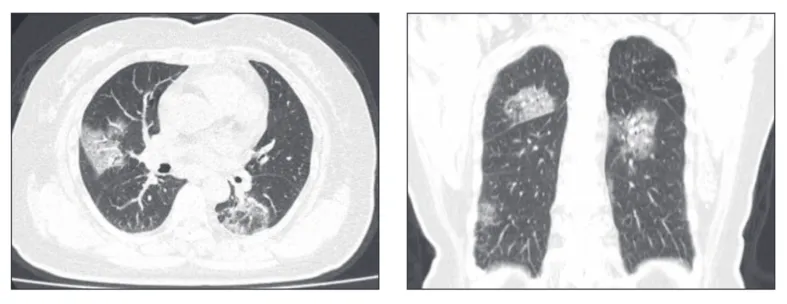

Для большинства патологий достаточно выполнения ультразвукового исследования легких в 6 зонах, описанного Д. Лихтенштейном (известное как Blue Protocol), или исследования легких по 8 точкам, описанного Дж. Вольпичелли. Однако анализ КТ-сканов у пациентов с COVID-19 показывает, что повреждения при этом заболевании являются мультифокальными и могут локализоваться в любой части легкого.

Выполняя ультразвуковое исследование легких в 6 зонах, велика вероятность пропустить патологию у пациента с COVID-19. Ультразвуковое обследование легких в 12 зонах повышает чувствительность к обнаружению поражений органа при COVID-19. Данный протокол был предложен итальянскими и китайскими специалистами (Buensenso, 2020 и Peng, 2020).

Наблюдаемые паттерны происходили в промежутке от легкого альвеолярного интерстициального паттерна до тяжелого двустороннего интерстициального паттерна и консолидации легких. В таблице 1 приведены типичные результаты УЗИ легких у пациентов с респираторным заболеванием COVID-19 в сравнении с данными КТ грудной клетки.

Ниже представлен ряд изображений патологических изменений, которые Вы можете увидеть при УЗИ легких пациентов с COVID-19. Эти изменения можно найти в любой части легкого, поскольку COVID-19 имеет мультифокальное распределение. Возможно сочетание областей нормального легкого и области с патологией. Патологические изменения легких могут отсутствовать в начале заболевания и при легком течении COVID-19, однако, по мере его прогрессирования, Вы можете наблюдать всё больше патологических изменений.

Ниже приведены примеры УЗ-картины легких пациентов с COVID-19.